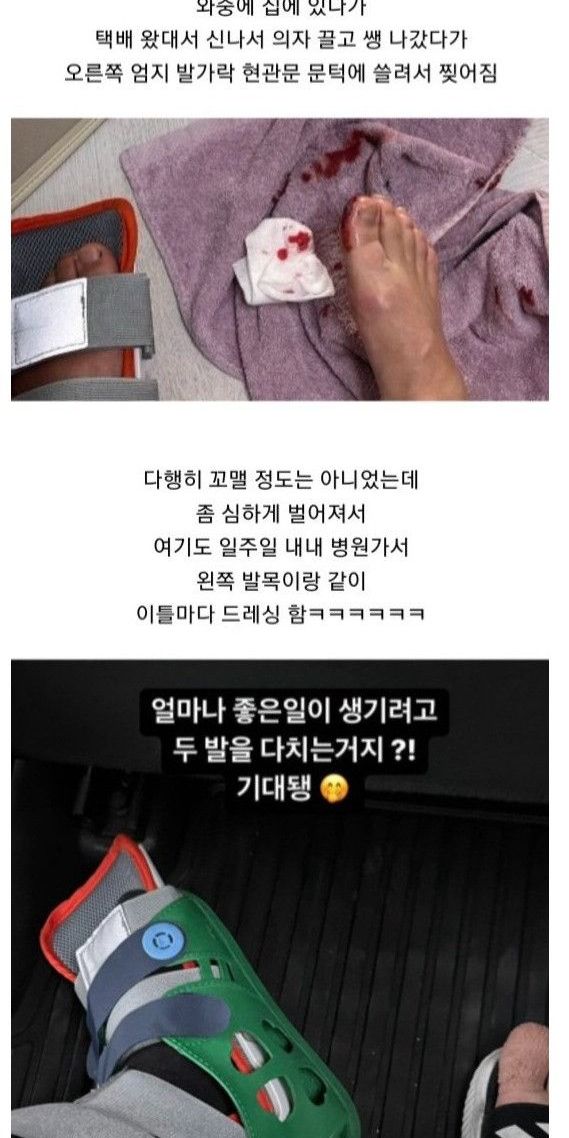

빙판길에서 자빠져 발목 부러져서 수술

수술했는데 하나도 안아픔